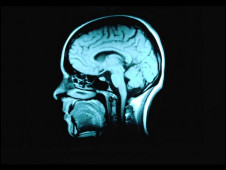

接受教育可降低患失智癥風險

科學家發(fā)現(xiàn)受教育時間越久,出現(xiàn)失智癥的機率就越低。

在過去10年當中,有關(guān)失智癥(dementia, 或稱癡呆)的各項研究一致顯示接受教育的時間越長的人,患失智癥的機會越低。

現(xiàn)在,英國和芬蘭的研究人員針對三個大型的有關(guān)老年化的研究進行分析,這三個大型研究一共觀察了872名已經(jīng)去世的老年人的大腦。

研究人員發(fā)現(xiàn),在他們?nèi)ナ乐?,他們大腦里出現(xiàn)失智癥的病變,與他們接受的教育程度沒有明顯關(guān)系。

但是接受教育程度越高的人,就越能適應老年之后帶來的種種問題,包括記憶力減退。

調(diào)查顯示,每接受教育一年,失智癥發(fā)生機率就會降低11%。

劍橋大學的漢娜·基格(Hannah Keage)表示,“我們發(fā)現(xiàn)在人死后,有的人大腦里出現(xiàn)失智癥病變,但這個人生前卻沒有失智癥癥狀。”

“研究顯示,接受教育能讓人更好的適應他們大腦老化帶來的問題?!?/p>